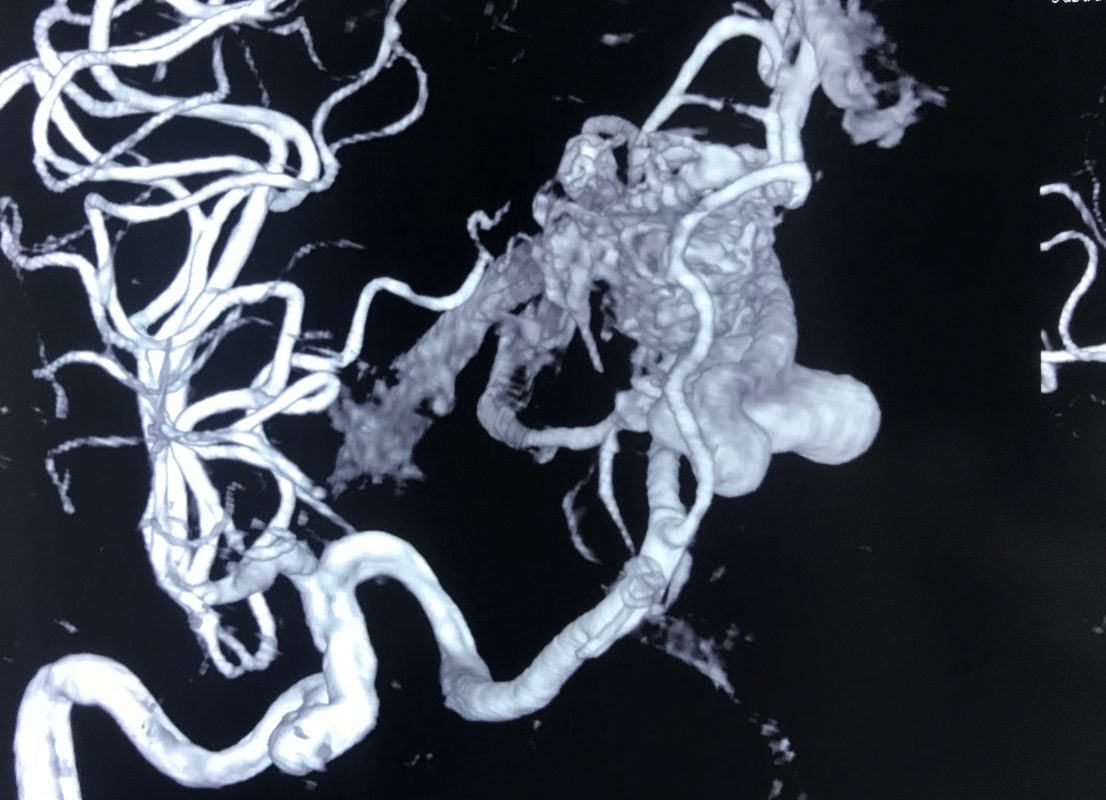

動静脈奇形(AVM)は、動脈と静脈の間の血液の流れを妨げる、まれな非癌性の血管のもつれです。

血液が動脈から毛細血管を通って静脈に流れるのではなく、AVM により血液が動脈から静脈に直接流れます。毛細血管は酸素を豊富に含む血液を細胞に分配することができないため、細胞が損傷を受ける可能性があります。

この侵襲性の低いタイプの手術は、長くて細い管であるカテーテルで到達できる AVM に対してのみ実行できます。

外科医はカテーテルを動脈に挿入し、AVM まで誘導し、AVM への血液の流れを止める物質を注入します。

- 医師は鼠径部または手首を小さく切開し、動脈にカテーテルを挿入します。 X 線画像を見ながら、医師は AVM に血液を供給している動脈にカテーテルを導きます。

- 次に医師は、小さな粒子、接着剤のような物質、金属製のコイルやプラグなどの塞栓物質を動脈に注入して動脈を硬化し、血流を遮断します。